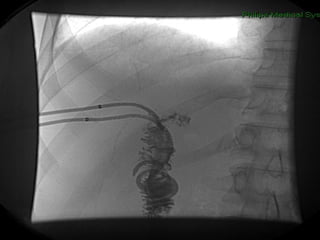

PAPEL DO RADIOLOGISTA DX TTO

Internalização dos Drenos

TROCA DE DRENOS